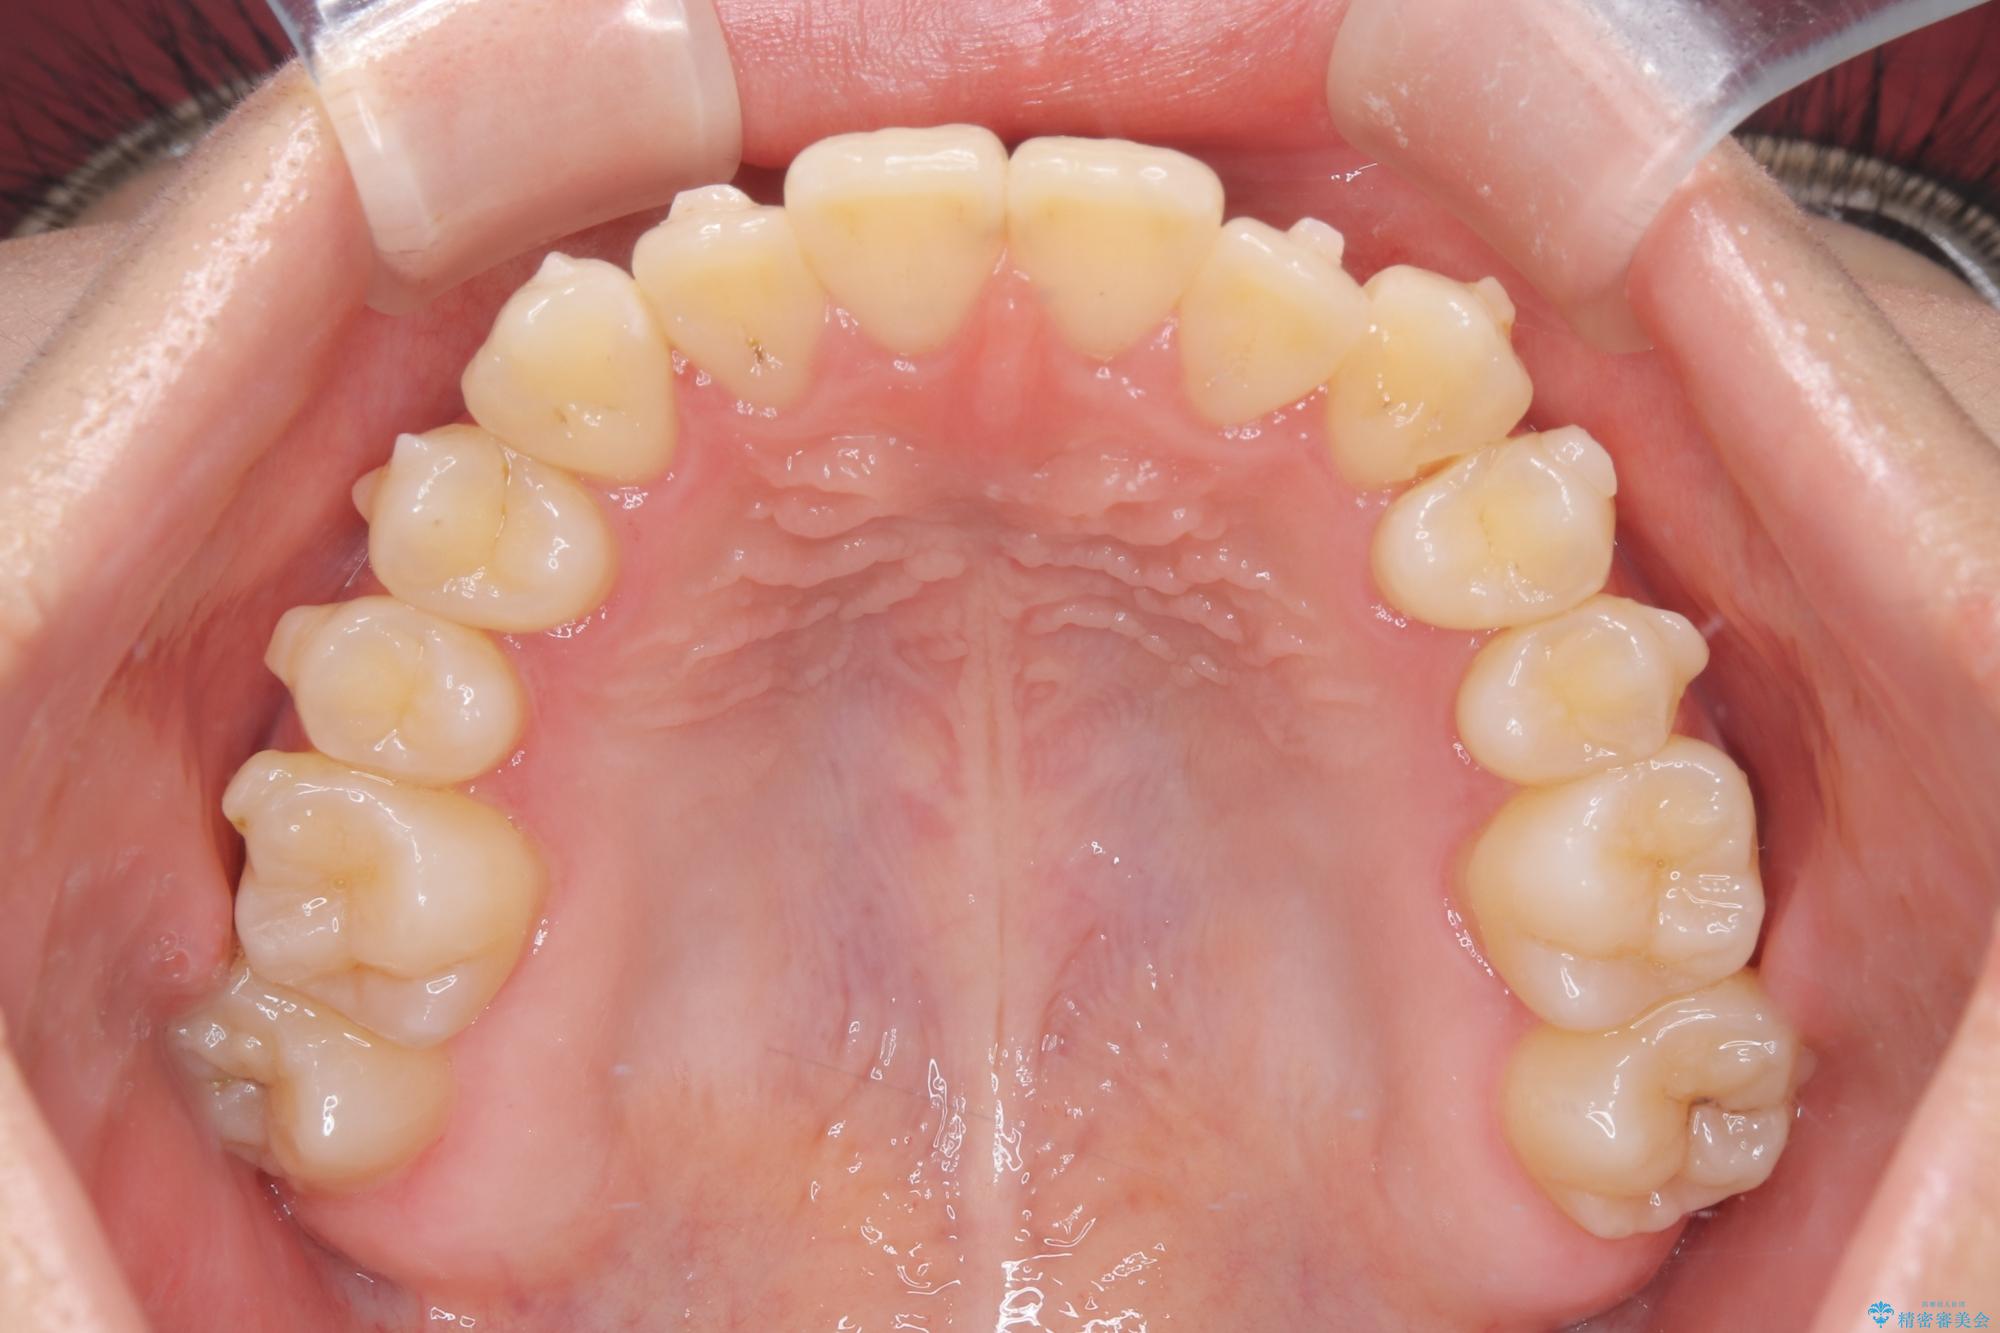

- 他院でインビザライン矯正を行っていたものの、通院先の閉院により治療が継続できなくなったとのことで来院されました。

診査の結果、すでに下顎前歯の抜歯が行われていましたが、マウスピースの適合が著しく悪くなっており、歯が計画通りに動いていない状態でした。また、歯を支える骨の厚みや歯肉の薄さを考慮すると、このままマウスピースによる傾斜移動を続けるのは歯肉退縮(歯茎が下がること)のリスクが非常に高いと判断。